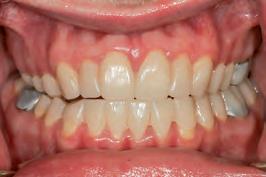

At this early stage of diagnostic work-up, prior to any operative intervention, the clinician and the technician can now communicate to each other and, most importantly, to the patient, in an understandable visual rhetoric, a precise end goal of treatment from which a meeting of the minds may be achieved (Figures 6 and 7).5

FIGURE 6: Prior to any irreversible and biologically expensive operative intervention, the tripartite stakeholders (patient, clinician and dental technician) of the reconstruction can achieve a precise meeting of the minds in a universally understandable visual rhetoric regarding the intended end goal of treatment.

FIGURE 7: Close-up extra-oral and intra-oral views illustrating satisfying contours of a proposed definitive restoration.